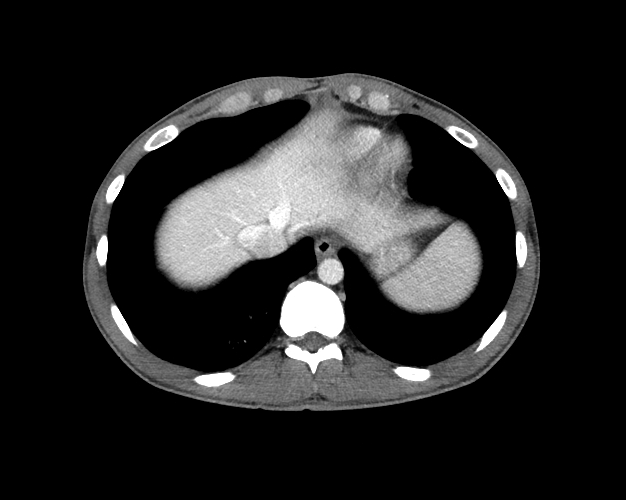

Body

Covers abdominal CT anatomy.